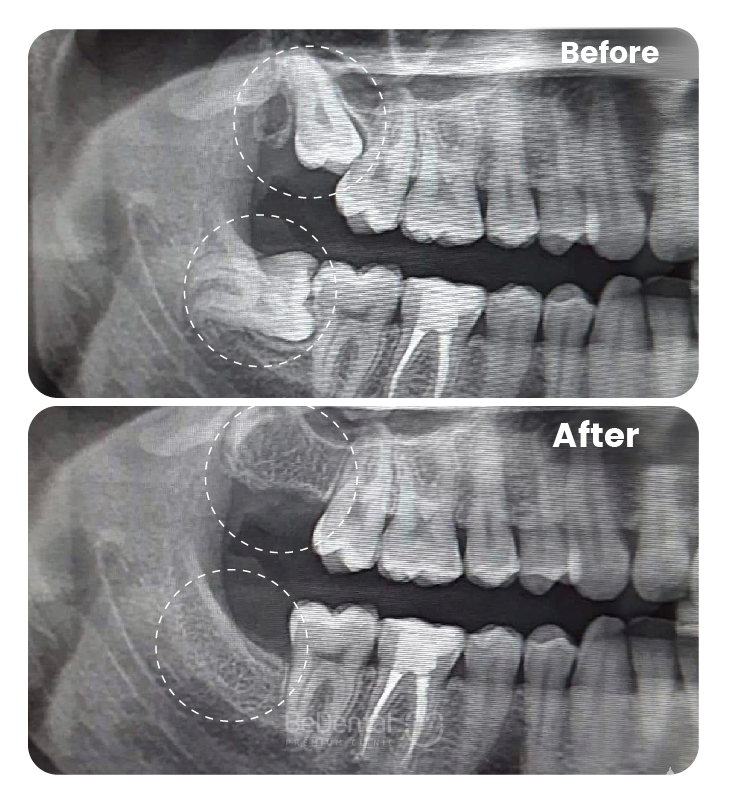

Bạn nên đến nha khoa ngay khi có các dấu hiệu như sưng tấy kéo dài, chảy mủ, hôi miệng kéo dài, đau khi há miệng hay sưng hạch cổ. Việc khám sớm giúp bác sĩ chụp X-quang đánh giá chính xác hướng mọc, mức độ lợi trùm và lên kế hoạch điều trị phù hợp — tránh tình trạng viêm lan rộng hoặc gây tổn hại cho răng số 7 và các mô liên quan.

- Khám chuyên sâu và chẩn đoán bằng hình ảnh X-quang kỹ thuật số, đánh giá chính xác hướng mọc và tình trạng mô lợi, xương hàm.